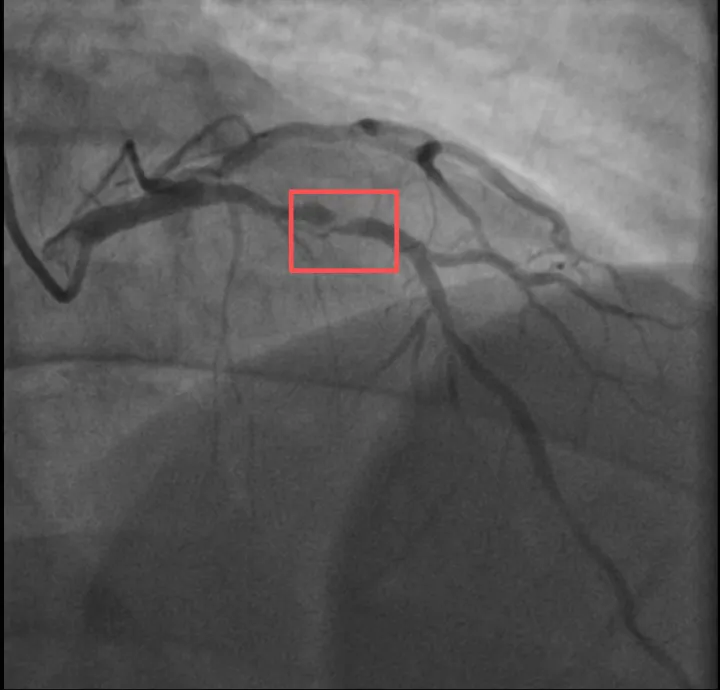

浙江医院心血管内科的医生分析,剧烈运动导致这位患者心脏的不稳定斑块破裂,进而造成前降支近段次全闭塞。所幸送医及时,孙先生的身体险情被化解。

介入治疗后影像图。